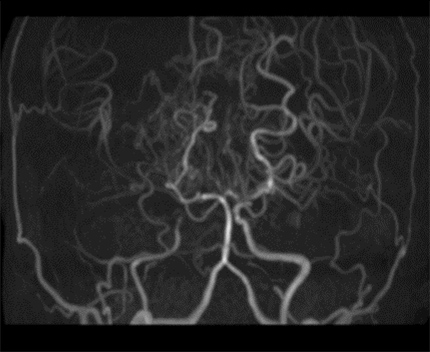

もやもや病では、頭蓋骨の頸動脈が詰まるか狭くなり、脳への血流が減少します。この閉塞を補うために、脳の基部で小さな血管が発達し、脳に血液を供給します。

もやもやは日本で初めて特定されました。もやもやとは日本語で「一吹きの煙」を意味し、脳の基部にある小さな血管の外観を指します。

「鈴木段階」は、もやもや病のさまざまな段階を表すために使用されます。血管の検査に使用される X 線の一種である血管造影は、通常、患者がどの段階にいるかを特定するために使用されます。

内頚動脈の末端枝はすべて狭くなります。深いもやもやの血管、つまり脳の基部に発達する小さな血管は、血管造影図で見ることができます。

より深いモヤモヤ血管が見られます。前大脳動脈と中大脳動脈を通る血流が損なわれます。